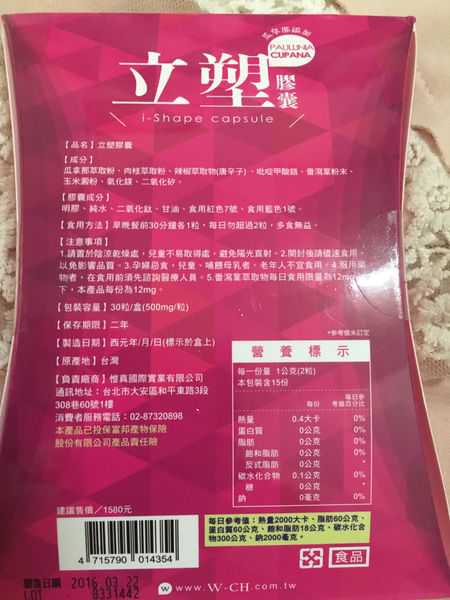

Supercut塑魔纖立塑膠囊的成分有:瓜拿那萃取粉、肉桂萃取粉、辣椒萃取物(唐辛子)、吡啶甲酸鉻、番瀉葉粉末、玉米澱粉、氧化鎂、二氧化矽。

之前上過相關課程,成分表是依照每項成分的多寡來排列順序,排在最前面的就是產品的主要成分!

食用方式:早晚餐前30分鐘各1粒,每日不超過2粒。(多食無益)

番瀉葉萃取物每日食用限量為12mg以下,